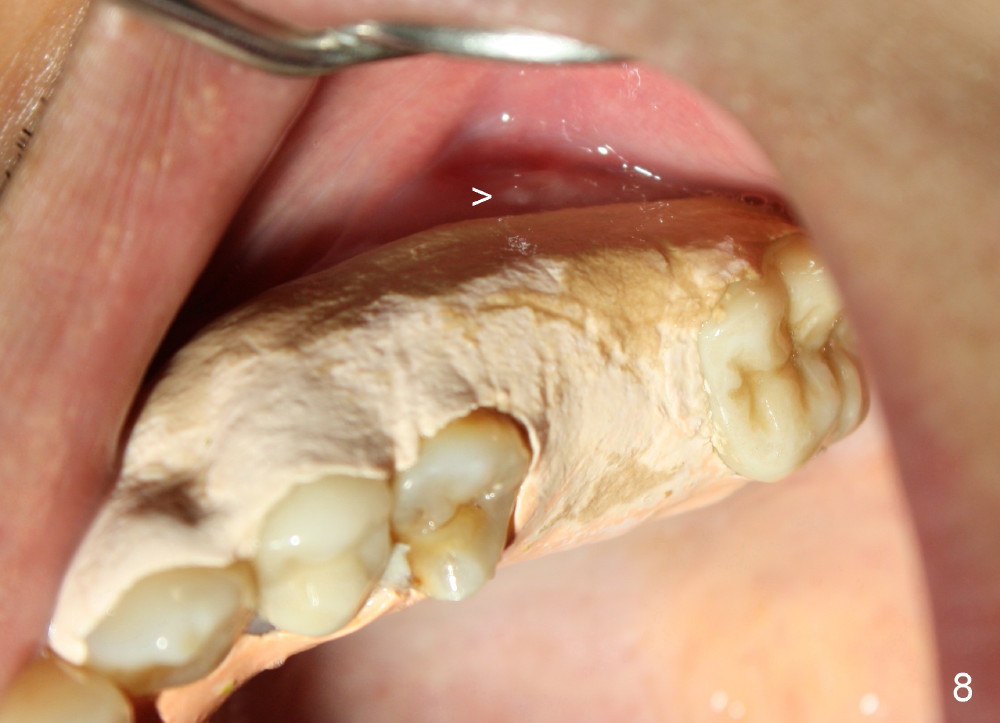

The upper left 1st molar is extracted with sectioning. The septum is large. A surgical fissure bur is used to initiate an osteotomy in the middle of the septum (Fig.1 <; P: palatal socket, MB: mesiobuccal socket), followed by tapping with resistance a 2 mm osteotome ~ 8 mm into the septum. It is tougher to drive 3 mm osteotomy. A 2.5 mm reamer is used to enlarge the osteotomy at 50 RPM at the same depth. Then it is relatively easy to tap 3 and 4 mm osteotomes at ~ 8 mm into the septum. A 4.5x17 mm tap is inserted 8 mm deep with binding to the septum. PA is taken (Fig.2). It appears that the sinus floor (black >) has been penetrated, but the osteotomy has not reached the apex (white >) of the palatal (P) socket. Then the tap is advanced ~ another 3 mm. When the tap is removed, the osteotomy (Fig.3 O) is slightly toward the buccal aspect of the extraction socket, but it has intact wall, including the mesiobuccal (>). The apex of the ostoetomy has no bone, but there is no air leakage. The next tap, 5x17 mm, is inserted shallower (~ 8 mm in the septum; to reduce potential trauma) with stability. However, 6x17 mm tap at the same depth does not obtain stability, since the osteotomy deviates severely mesiobuccally (Fig.4 arrow) with breakdown of the mesiobuccal wall. So the osteotomy has to be deeper in order to achieve stability of 6x17 mm tap (by engaging into more apical bone). A 7x17 mm tap is then intended to be inserted to close the socket as much as possible, but as it is being inserted, the osteotomy is more severely deviated and tilted mesiobuccally with the original mesiobuccal wall further being broken down (not shown). It appears to compromise stability. Mixture of autogenous bone from reamer, allograft and synthetic bone is placed in the mesiobuccal and palatal sockets before placement of the 6x17 mm implant (Fig.5 I). Unfortunately some of graft blocks the apical osteotomy. To clear the blockage, some of previous osteotome and taps are re-inserted. The result is in fact beneficial, as bone graft (G) is pushed upward. Prior to implant placement, nose blowing test does not produce air leakage. More allograft is placed in the coronal portion of the sockets (Fig.6 G); an abutment with precut slots is placed (A) with intention of better holding perio dressing in place after placement of a collagen dressing (Fig.7 M). A temporary crown may be placed when the perio dressing is dislodged. The provisional is to keep the membrane and bone graft in place. The patient returns for follow up 1 week postop. He is symptom free. The abscess appears to be resolving (Fig.8 >); the perio dressing remains in place.

One week later, the lingual portion of the perio dressing is dislodged. The wound is healing, while part of bone graft is exposed (Fig.9 ^). The remaining perio dressing is removed before repacking (Fig.10): it appears that the buccal fistula has disappeared, as compared to preop.